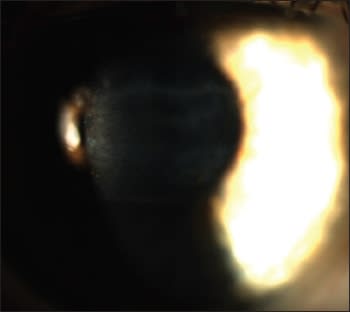

Our patient is a 19-year-old female who suffered a herpes simplex infection to the right eye at age 6 with a recurrence at age 16. Since that time she has experienced blurred vision secondary to a diffuse central corneal scar (Figure 1). Her condition is currently controlled with acyclovir b.i.d. p.o., and slit lamp examination confirmed no active herpes infection. Visual acuity without correction was OD 20/100 and OS 20/15. Manifest refraction OD was +1.00 −5.50 x 125 VA 20/40. Corneal topography revealed simulated keratometric readings of OD 41.12 @ 125/47.12 @ 035 with 5.87D of corneal astigmatism and OS 43.00 @ 035/43.50 @ 125 with 0.50D of corneal astigmatism (Figure 2).

Figure 1. Patient's post-HSV scar.